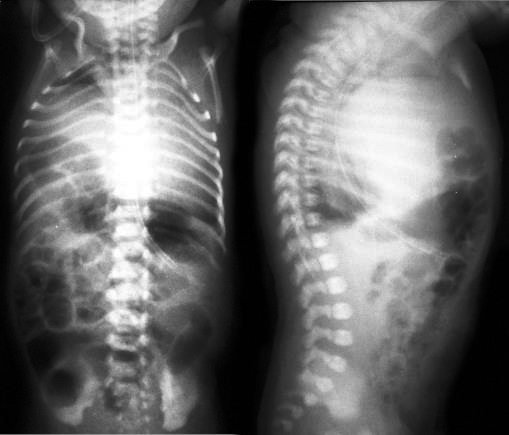

Ребенок Б. поступил в отделение реанимации новорожденных НОДКБ 12.05.2017 на вторые сутки жизни (дата рождения 11.05.17). Доставлен неонатальной реанимационной бригадой Центра медицины катастроф из Центральной районной больницы (230 км от Нижнего Новгорода) с диагнозом: синдром дыхательных расстройств, дыхательная недостаточность I степени, перинатальное поражение ЦНС, синдром угнетения. Ребенок от пятой беременности, третьих преждевременных родов на сроке 36 нед. гестации, вес при рождении 2110 г, оценка по шкале Апгар 3/6 баллов. Проводились реанимационные мероприятия: санация верхних дыхательных путей, ИВЛ мешком Амбу, после чего ребенок закричал. От кислорода зависим с первых суток жизни. При поступлении: состояние тяжелое, дотация кислорода через маску, гипотония, гипорефлексия, дыхание с участием вспомогательной мускулатуры, ослабленное с обеих сторон. Тоны сердца приглушены. При рентгенографии легких при поступлении – подозрение на диафрагмальную грыжу справа (рис. 6).

Рис. 6. Рентгенограмма органов грудной клетки. Признаки правосторонней диафрагмальной грыжи.

По УЗИ брюшной полости – без патологии. На рентгенографии желудочно-кишечного тракта (ЖКТ) с проходящим барием – петли кишечника определяются в правой половине грудной клетки. На 4-е сут проведена МСКТ легких, которая подтвердила диагноз правосторонней диафрагмальной грыжи, содержимое – петли кишечника. Ребенок прооперирован 17.05 – лапаротомия в правом подреберье, проведена пластика правого купола диафрагмы (щель Бохдалека) собственными тканями по методике «за ребро». Послеоперационный период протекал тяжело. Отмечалось «парадоксальное дыхание» с втяжением податливых мест грудной клетки на вдохе, вероятно, обусловленное врожденной патологией развития и иннервации диафрагмы, усугубленное гипоплазией правого легкого. На 4-е сут после операции – самостоятельное дыхание с дотацией кислорода через маску, гемодинамических расстройств не отмечено (рис. 7).

Рис. 7. Рентгенограмма органов грудной клетки, выполненная на 6-е сутки после операции.

На 13-е сут после операции отмечалась отрицательная респираторная динамика – усиление втяжения грудной клетки, ослабление дыхания слева. По рентгенограмме – подозрение на левостороннюю диафрагмальную грыжу (рис. 8). Ребенок переведен на ИВЛ, начата интенсивная терапия в режиме предоперационной подготовки. По эхокардиограмме – декстракардия, расширение правых отделов сердца. Отмечались постоянные срыгивания при кормлении, проведена декомпрессия желудка, «голодная пауза». На рентгенографии ЖКТ с проходящим контрастом – перемещение части желудка и петель кишечника в передние отделы левой грудной полости, затемнение левых легочных полей (рис. 9).

Рис. 8. Рентгенограмма органов грудной клетки. Признаки левосторонней диафрагмальной грыжи.

Рис. 9. Рентгеноконтрастное исследование с пассажем контраста для подтверждения левосторонней диафрагмальной грыжи. Перемещение части желудка и петель кишечника в передние отделы левой грудной полости, затемнение левых